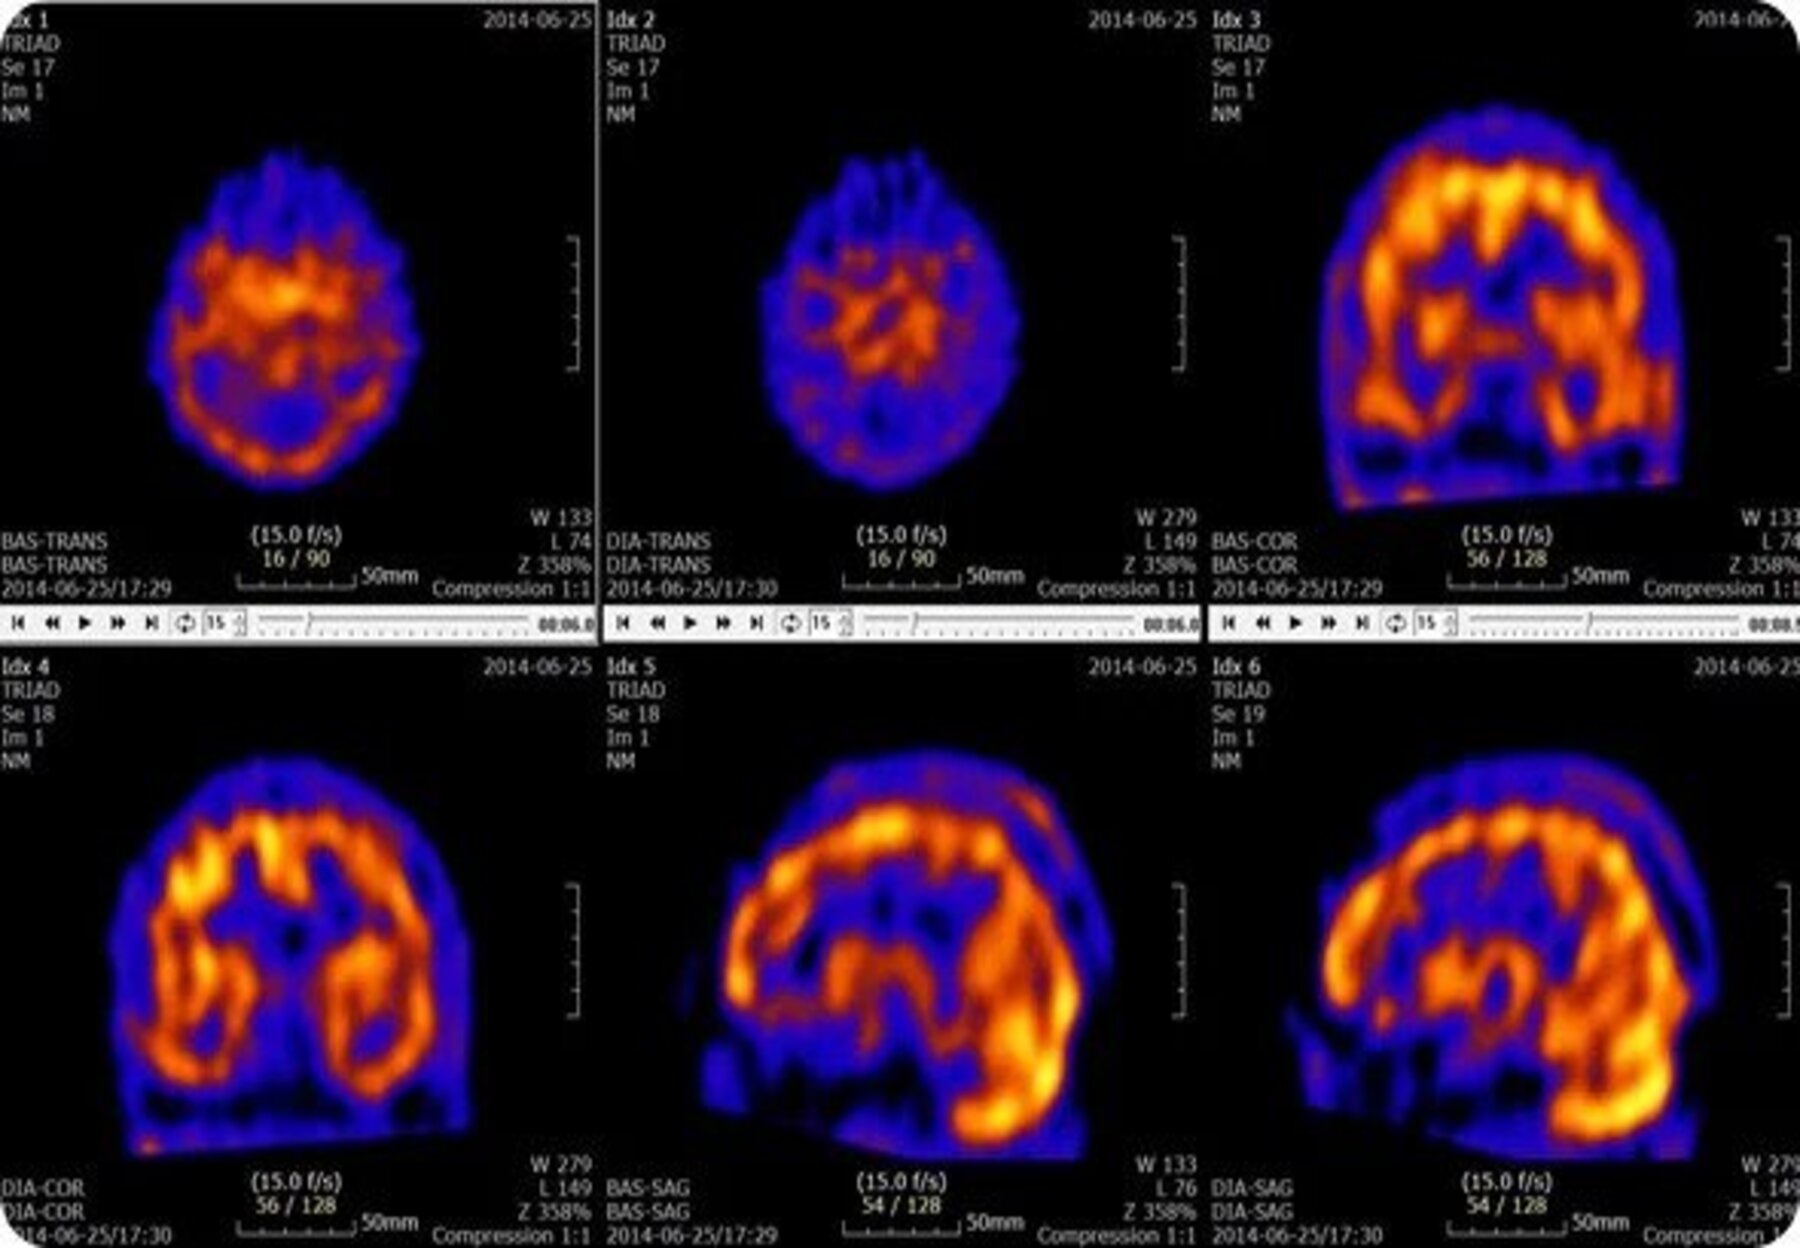

The specialized computer during a SPECT scan collects the information emitted by the gamma rays and displays it on the CT cross-sections. These cross-sections can be added back together to form a 3D image of your brain. These 3D images created using nuclear imaging technologies in a SPECT scanner are primarily used to view how blood flows through arteries and veins in the brain as it can detect reduced blood flow to injured sites more sensitively in comparison to other imaging methods.

Instead of using photons (PET scans), gamma rays within tracers are directly administered through an IV, which then a gamma camera can be used to render functional images of the brain. This application of chemistry and atomic structure allows doctors to specifically diagnose dementia, perform evaluations of medically uncontrolled seizures pre surgery, and locate clogged blood vessels.